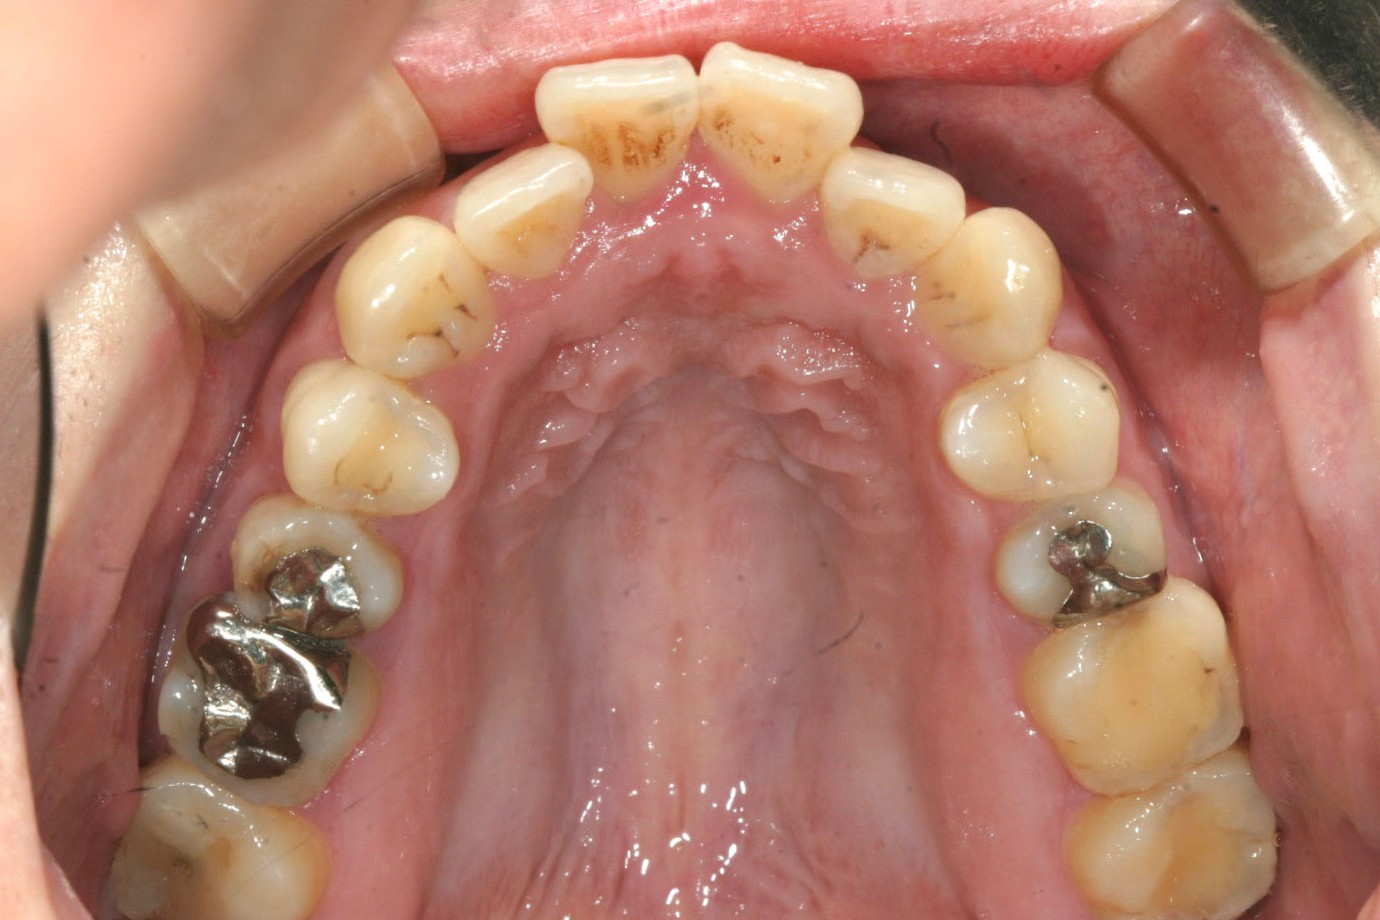

小臼歯を抜きアーチを広げる事で出っ歯を引っ込めました・

下顎もアーチを広げ綺麗に並びました。